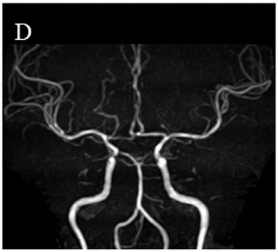

这种变异理论上致病性更高,但她的头部MRI仅提示颅内动脉壁不规则(图D),从未出现过头晕、肢体无力等烟雾病典型症状,脑部也没有烟雾病特有的血管异常网。

血管造影显示烟雾病